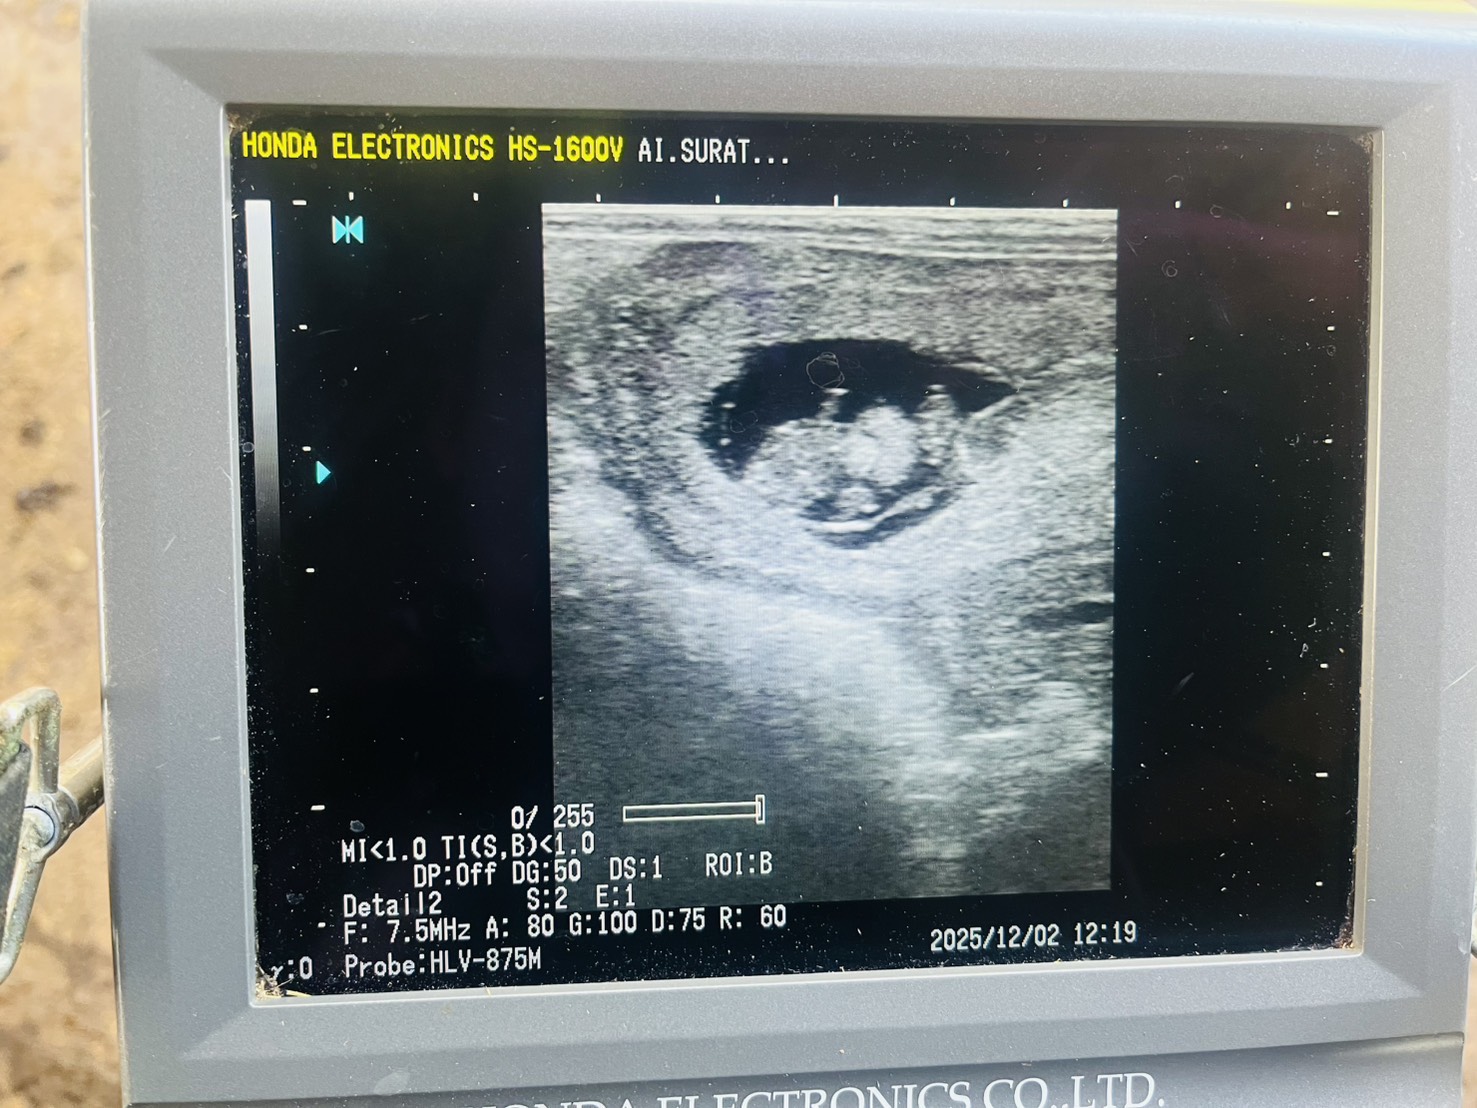

- ล้วงตรวจท้องโคนม

- ล้วงตรวจระบบสืบพันธุ์และฉีดวิตามินบำรุง